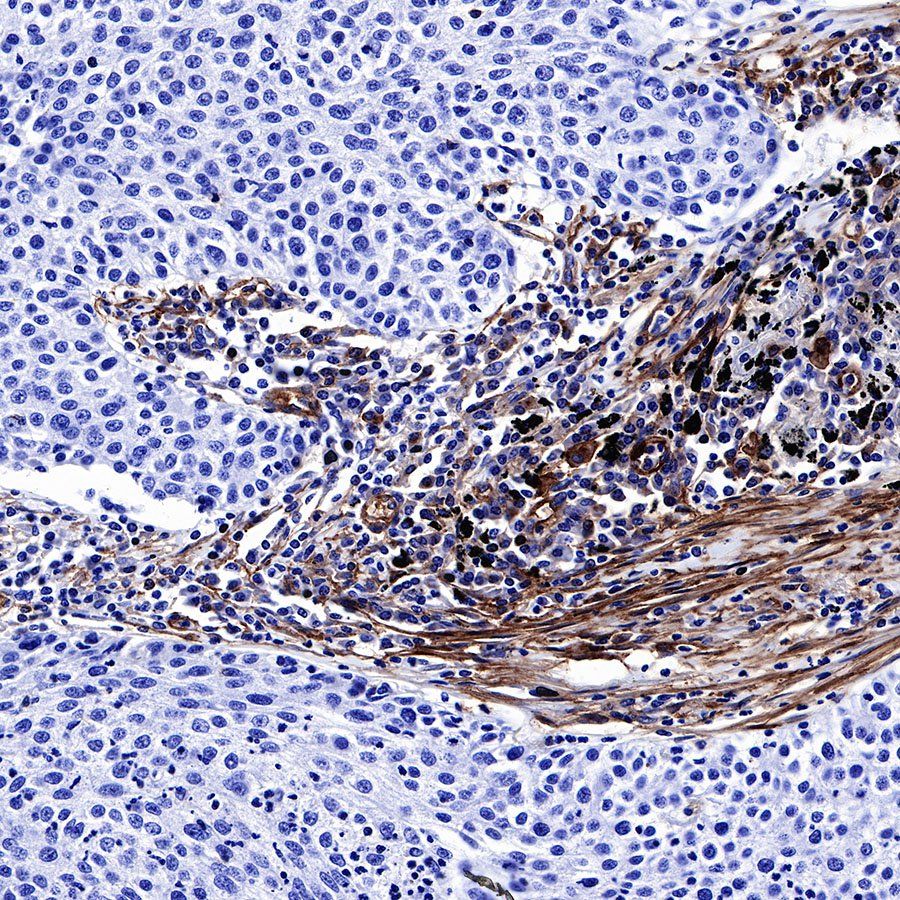

IHC shows positive staining in paraffin-embedded human lung adenocarcinoma. Anti-CD39 antibody was used at 1/500 dilution, followed by a HRP Polymer for Mouse & Rabbit IgG (ready to use). Counterstained with hematoxylin. Heat mediated antigen retrieval with Tris/EDTA buffer pH9.0 was performed before commencing with IHC staining protocol.